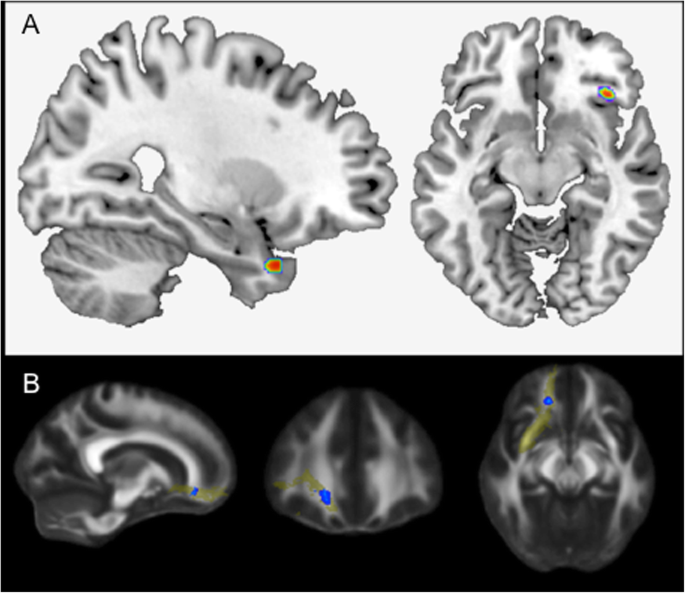

VBM data

In this sub-sample of N = 342, paternal age was linearly correlated with increases in gray matter in the right hippocampal formation (MNI coordinates xyz: 27; 15; − 33, cluster extent 82 voxels) as well as the right inferior frontal gyrus (IFG; MNI coordinates: 38; 27; − 9, cluster extent 50 voxels) (see Fig. 1a). Maternal age was linearly correlated with decreased gray matter volume in the right IFG (MNI coordinates: 38; 27; − 11, cluster extend 54 voxels, see Supplementary Fig. 1.

a Advanced paternal age is associated with increased right hippocampal volume (N = 342). Effects of paternal age (p < .001, uncorrected) on volume within the right hippocampal formation (cluster extent = 82 voxels) and right inferior frontal gyrus (cluster extent = 50 voxels). b Advanced paternal age is associated with white matter microstructure in the right uncinate fasciculus (N = 222). The effect of paternal age on the fractional anisotropy in the right uncinate fasciculus as a predefined region-of-interest (based on the John Hopkins University White-Matter Tractography Atlas)

DTI data

In this sub-sample of N = 222, voxelwise analysis of the FA maps revealed a positive linear relationship between paternal age and white matter microstructure in the right uncinate fasciculus (UF; MNI coordinates xyz: 27; 15; − 33; p < 0.05, FWE-corrected; see Fig. 1b), connecting the frontal with the temporal lobe.